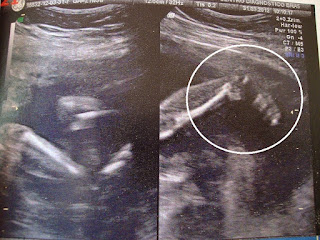

sem ar nos pulmões, seu bebê começa a fazer alguns exercícios de respiração. Os

cinco sentidos estão se desenvolvendo com rapidez. Com 26 semanas, exames de

imagem cerebral em fetos mostram que há reação ao toque. Se você aproximar uma

luz forte da barriga, o bebê vai virar o rosto, o que, segundo pesquisadores,

indica que o nervo óptico está funcionando. Você